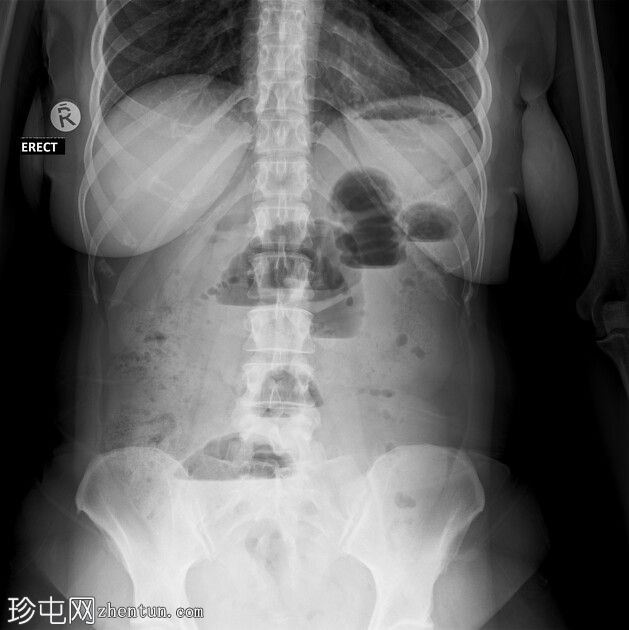

2.jpeg

正位片

立位片可见多个气液平面,高度和宽度不一

结肠内气体稀少

无气腹